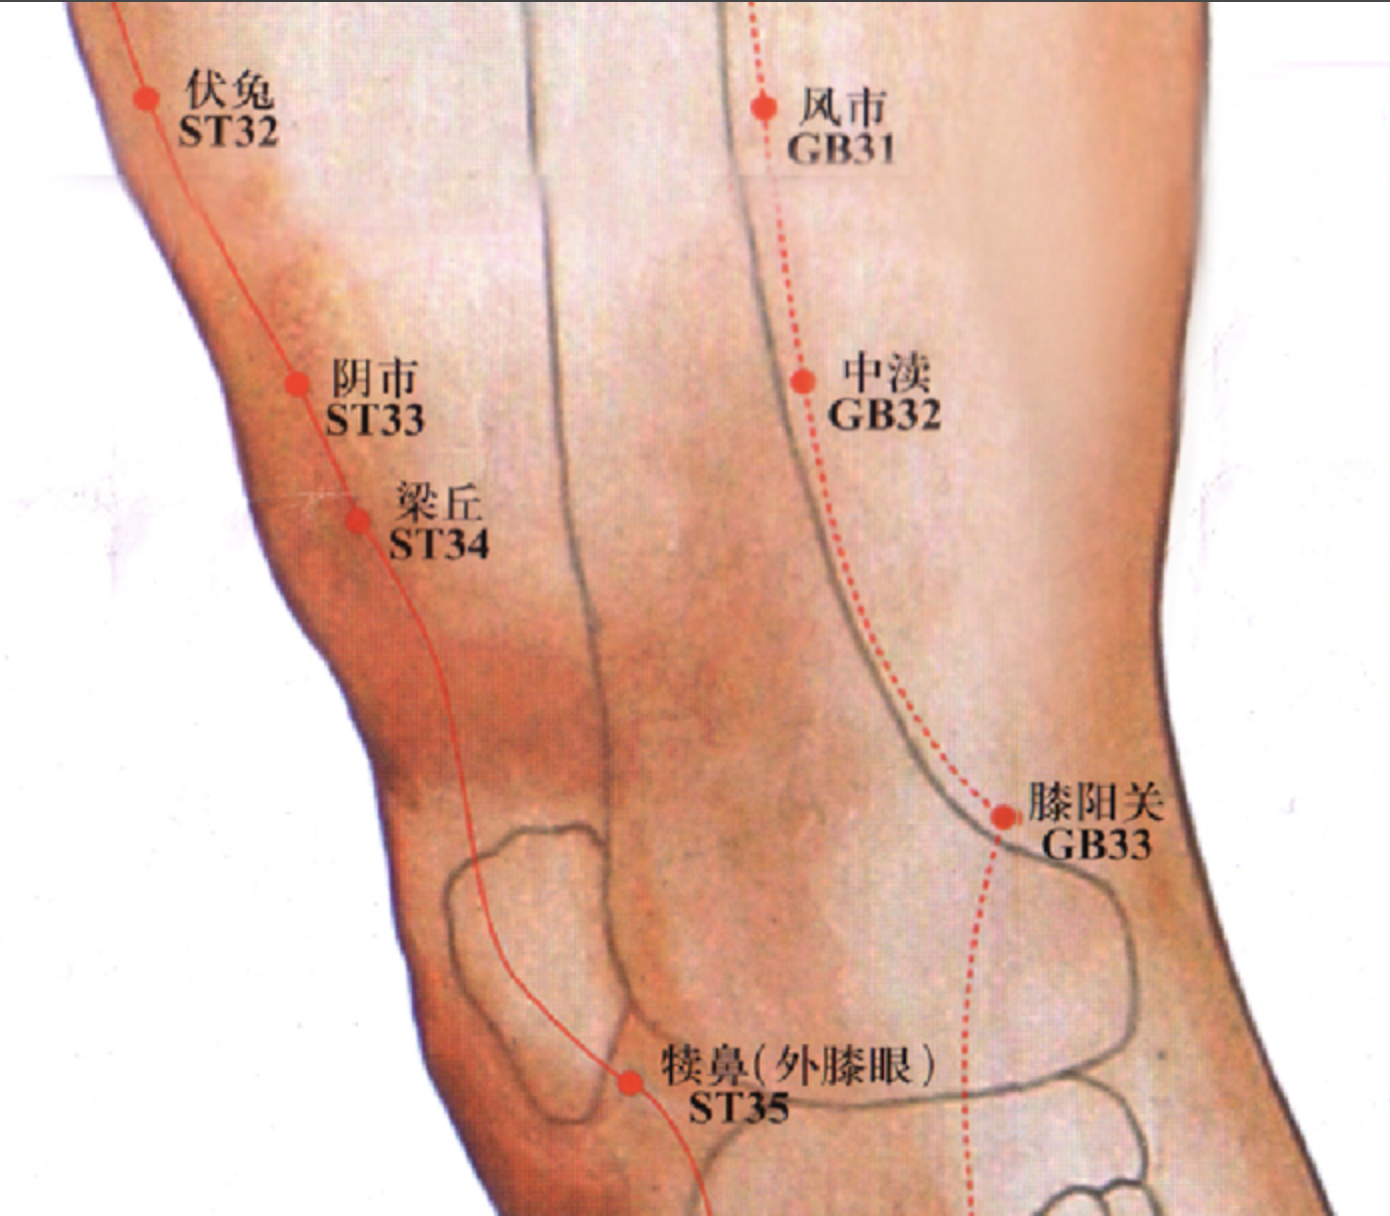

【(十一)足少阳胆经(图 10-29-1)】

2、歌诀 少阳足经瞳子髎,四十四穴行迢迢,听会上关颌厌集,悬颅悬厘曲鬓翘,率谷天冲浮白次,窍阴完骨本神邀,阳白临泣木窗辟,正营承灵脑空摇。风池肩井渊腋部,辄筋日月京门标,带脉五枢维道续,居髎环跳风市招,中渎阳关阳陵泉,阳交外邱光明宵,阳辅悬钟邱墟外,临泣地五会侠溪,第四指端窍阴毕。

3、经脉循行 起于目外眦(瞳子髎),向上到额角,返回下行至耳后,沿颈部向后交会大椎穴,再向前入缺盆部,入胸过膈,联络肝脏,属胆,沿胁肋部,出于腹股沟,经外阴毛际,横行入髋(kuān)关节(环跳)。

耳后支部:从耳后入耳中,出走耳前,到目外眦处向后向下经颊部会合前脉与缺盆部。下行腋部,沿侧胸部,经季肋和前脉会于髋关节后,再向下沿大腿外侧,行于足阳明和足太阳经之间,经腓(féi)骨前直下到外踝前,进入足第 4 趾外侧端(足窍明)。

风市

【定位】 在大腿外侧部的中线上,当腘(guó)横纹上 7 寸。或直立垂手时,中指尖处。

【主治】 中风半身不遂,下肢痿痹、麻木,遍身骚痒,脚气。

【配伍】 配风池、大杼、大椎、命门、关元、腰阳关、十七椎治中心型类风湿。

【刺灸法】 直刺 1 ~ 1.5 寸;可灸。